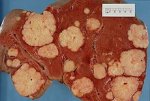

ЛимфогранулематозЛимфогранулематоз — тяжелое общее заболевание, протекающее с опухолевидными разрастаниями лимфатических... ЛимфогранулематозЛимфогранулематоз — тяжелое общее заболевание, протекающее с опухолевидными разрастаниями лимфатических...